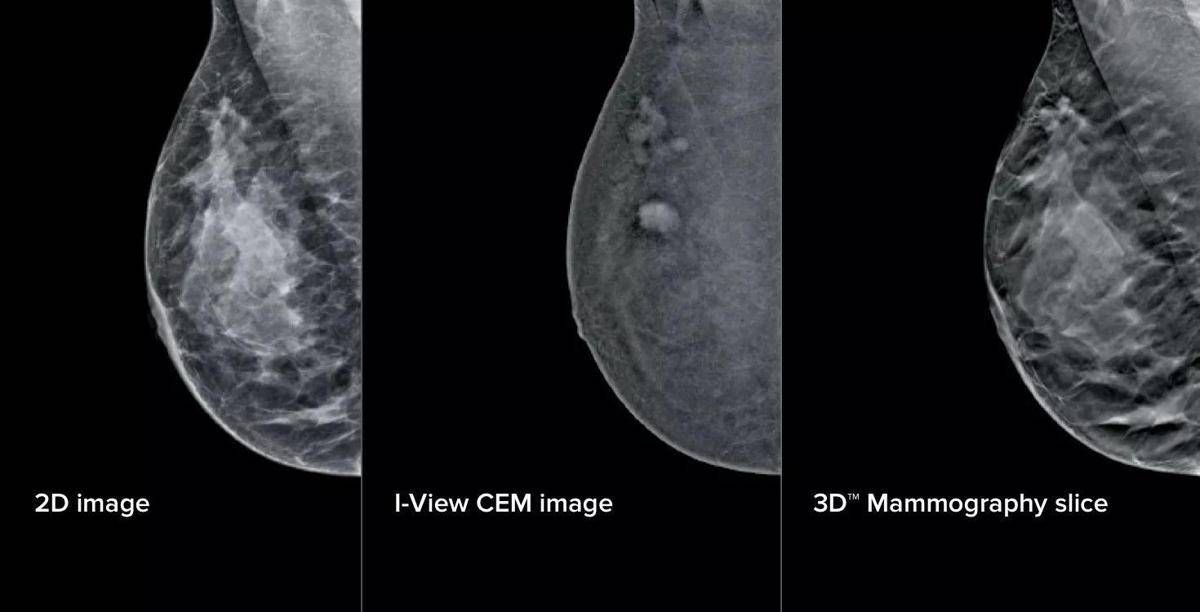

L’aggiornamento – illustra il San Camillo – si compone di elementi fisici e virtuali in due ambiti principali: la mammografia con refertazione e la biopsia mammaria. Sul fronte della refertazione, è stata introdotta una nuova workstation con monitor ad altissima risoluzione e strumenti avanzati di analisi delle immagini. Un software dedicato consente di valutare in modo oggettivo la densità del tessuto mammario, un elemento importante perché associato al rischio di tumore al seno. A questo si aggiunge un software che analizza struttura e densità del tessuto mammario, tecnologia di tomosintesi avanzata che riduce del 66% il numero di slice – le ‘fettine’ spesse 1 mm di tessuto mammario acquisite dal mammografo – mantenendo le stesse informazioni diagnostiche. Meno immagini da scorrere significa meno affaticamento: una riduzione del carico cognitivo per il radiologo stimata intorno al 13%, con benefici concreti soprattutto nelle sessioni di lettura multipla. A supporto dei medici – prosegue la nota – è stato integrato anche un sistema di intelligenza artificiale che evidenzia automaticamente le aree sospette sulle singole slice, come microcalcificazioni o alterazioni del tessuto, e fornisce indicazioni utili per la priorità di lettura. Studi preliminari indicano “un miglioramento della capacità di individuare lesioni fino al 9%”.

Sul fronte della biopsia mammaria, i mammografi di ultima generazione consentono di eseguire la procedura direttamente a partire da immagini con contrasto, unendo in un unico passaggio la localizzazione della lesione e il prelievo bioptico. Per la paziente questo si traduce in un percorso interamente nello stesso reparto, senza la necessità di ricorrere alla risonanza magnetica chiusa. Un apposito dispositivo meccanico permette inoltre di raggiungere anche le lesioni in posizioni difficili.

Aggiunge Francesca Svegliati, responsabile Uosd Diagnostica per immagini in senologia: “Oggi abbiamo strumenti che ci permettono di essere ancora più precisi, individuando dettagli e microcalcificazioni difficili da rilevare a occhio nudo. Questo rafforza la sicurezza diagnostica e ci consente di offrire risposte più rapide. L’upgrade più importante riguarda le biopsie guidate con mezzo di contrasto (Cem): poter sottoporre a biopsia lesioni non altrimenti evidenziabili o visibili solo in risonanza magnetica ci consente di raggiungere una precisione nella stadiazione locale già in reparto senza ricorrere a procedure diagnostiche – biopsia Rm guidata – che risultano molto più impattanti sul percorso della paziente. Per chi si rivolge a noi significa meno attesa e meno tensione, con un percorso più fluido, semplice e accurato”.